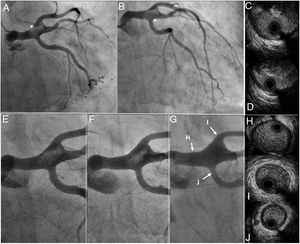

Baseline and follow-up angiographies and intravascular ultrasound.

(A, B) Baseline coronary angiography showed a coronary mass in distal left main coronary artery (white asterisks); Online-Video 1.

(C-D) Baseline intravascular ultrasound showed a large intraluminal mass, presenting a variable gray scale with speckling, suggestive of thrombus.

(E-G) Progressive and complete thrombus dissolution on coronary angiographies; Online-Video 2-4.

(H-J) Final intravascular ultrasound demonstrated the absence of thrombus and atherosclerotic disease.

Intracoronary half-dose of tenecteplase and abciximab was administered. After initial management, an aggressive in-hospital antithrombotic strategy with aspirin, ticagrelor and intravenous UFH was followed. A total of three serial coronary angiographies were performed over the next two weeks, showing a progressing reduction of thrombus burden until there was complete dissolution (Figure 1E, 1F, 1G, Online-Video 2-4). Finally, IVUS reconfirmed the absence of coronary parietal disease (Figure 1H-1J). Patient was discharged under aspirin, clopidogrel and acenocumarol for one month, followed by aspirin and acenocumarol. Twelve months later, the patient remained asymptomatic without bleeding events.